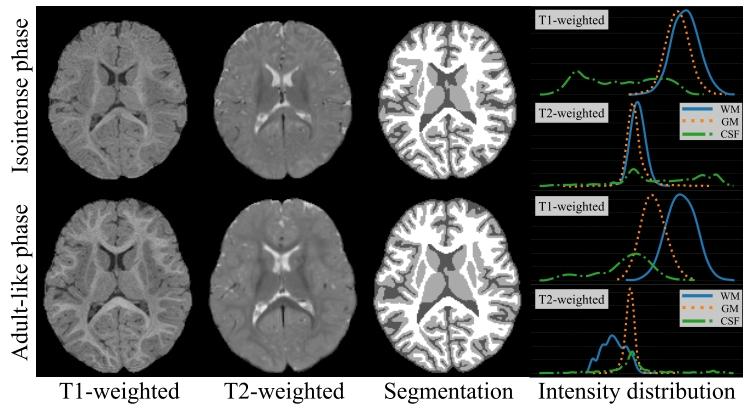

婴儿脑部图像精确组织分割的研究背景与方法设计 将婴儿脑部图像精确分割为白质(WM)、灰质(GM)、脑脊液(CSF)等不同感兴趣区域,是实现大脑结构与生物标志物(如皮层厚度、脑沟深度、脑回指数)精细化量化分析的基础步骤。在出生后第一年,随着脑部快速髓鞘化与成熟过程,婴儿脑部磁共振(MR)图像呈现出三个显著阶段:a)婴儿期阶段(≤3月龄)、b)等信号阶段(6~9月龄)、c)类成人阶段(≥12月龄)。图1展示了等信号阶段(上图)与类成人阶段(下图)的典型婴儿脑部磁共振图像,及其分割图与各组织的信号强度分布。可见,在等信号阶段,T1加权和T2加权磁共振图像中白质与灰质的信号强度高度重叠;而类成人阶段的组织对比度显著更高,尤其是在T1加权磁共振图像中。因此,等信号阶段图像的组织分割难度极大,类成人阶段图像则相对易于分割。 在深度学习时代之前,已有诸多研究致力于等信号阶段图像的分割,例如通过将人工标注图谱配准到目标图像来实现分割。然而,由于等信号阶段图像的组织对比度较低,难以在图谱与目标图像间建立体素级对应关系,这一问题成为标签传播法实现高分割精度的瓶颈。近年来,基于学习的方法被提出以提升分割性能[7]-[11]。这些方法通过手工设计特征或深度卷积神经网络(CNN)自动学习特征,以判别式方式预测组织标签。但由于等信号阶段图像的组织边界模糊,且特征表示能力仍有限,这类方法得到的分割结果往往与真实脑组织拓扑结构存在较大偏差。 为解决上述问题,有研究考虑在分割过程中引入组织解剖结构作为全局先验,以校正分割结果的拓扑结构。但总体而言,这些方法所用的解剖先验知识仍基于手工设计特征,难以解释人类大脑中复杂的组织解剖结构。针对上述挑战,近年有研究提出直接利用易于分割的类成人阶段图像指导分割过程,并设计风格迁移网络,使类成人阶段图像中的解剖先验知识能有效用于等信号阶段图像分割。但这类方法的成功风格迁移需依赖大量带标注的等信号阶段与类成人阶段图像,而这类数据往往难以获取。 已有研究充分证实,正常出生后婴儿脑部的皮层脑回模式在早期发育过程中基本保持稳定。基于此,本文提出一种多视角分割流程,通过充分利用类成人阶段图像中的有用解剖先验知识,实现稳健的等信号阶段婴儿脑分割。具体而言,一方面,将类成人阶段图像迁移为与等信号阶段图像具有相似组织对比度的图像,利用迁移后的图像对“等信号视角分割网络”进行预训练;另一方面,将等信号阶段图像迁移至类成人视角,借助增强的组织对比度训练“类成人视角分割网络”。不同视角的分割网络构成多路径架构,通过多视角学习进一步提升分割性能。 由于双向保留解剖结构的风格迁移是类成人阶段图像发挥作用的关键,本文设计了一种解纠缠循环一致对抗网络(DCAN),并精心设计正则化项,以在等信号阶段与类成人阶段图像间精确迁移组织对比度。该过程无需组织标签即可在风格迁移中保持结构一致性。本文采用NDAR[18]与iSeg-2019两个数据集对所提方法进行评估,实验结果表明,该方法性能显著优于当前主流方法,且具有统计学意义。

Fig. 1. Representative MR images, corresponding segmentation maps,and the intensity distribution of each tissue of the isointense phase (top)and the adult-like phase (bottom) infant brain.

图1 等信号阶段(上图)与类成人阶段(下图)婴儿脑部的典型磁共振(MR)图像、对应分割图及各组织的信号强度分布 (注:图中“分割图”通常以不同颜色区分白质、灰质、脑脊液等组织;“信号强度分布”一般以直方图形式呈现,可直观反映等信号阶段白质与灰质信号高度重叠、类成人阶段组织信号区分度高的特点,为两类阶段图像的分割难度差异提供可视化依据。)